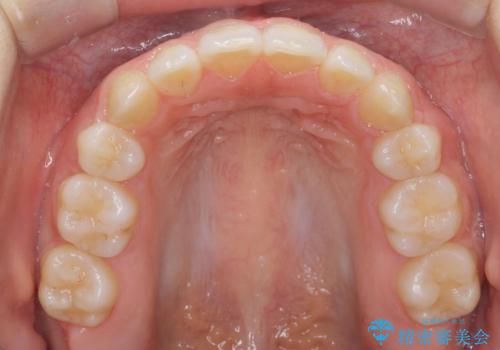

前歯、奥歯ともに反対咬合になっており、また上顎の前歯が少し突出気味でした。

上下左右の小臼歯を抜歯しています。

時間はかかりましたがしっかりかみ合わせから治すことができました。

口元の突出も改善しており理想的な横顔になりました。